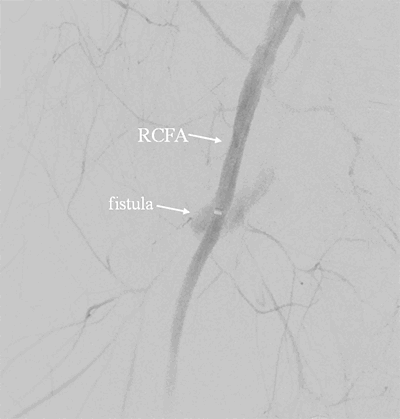

An arteriogram of the right extremity revealed an AVF at the junction of the common femoral vein and superficial femoral artery with no distal flow (Figure 4). This was unable to be traversed and the decision was made to transfer patient back to the operating room with endovascular capabilities for further operative intervention.

Figure 4. Right sided AVF. Catheter seen inserted into femoral artery for retrograde contrast injection, with fistula visualized and opacification of the venous system, with no flow in the distal artery. RCFV=right common femoral vein.